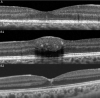

Purpose: To determine the prevalence of a central hyperreflective line in eyes with full-thickness macular holes (FTMH) and lamellar macular holes (LMH) and to elucidate the pathoanatomic importance of this optical coherence tomography (OCT) sign.

Methods: This retrospective analysis evaluated patients with FTMH and LMH at the Stein Eye Institute. Clinical data was collected and SD-OCT volume scans were analyzed for the presence of a central vertical hyperreflective line in 3 separate cohorts: patients with SD-OCT preceding FTMH development, patients with SD-OCT after pars plana vitrectomy (PPVT) treatment for FTMH, and patients with SD-OCT of LMH.

Results: In total, 93 eyes with FTMH and 88 eyes with LMH were identified. Of the 93 FTMH eyes, SD-OCT volume scans were available before development of the FTMH in 12 eyes. Of these, 6 (50%) displayed a vertical hyperreflective line preceding the development of the FTMH. Fifty-one eyes underwent PPVT with resolution of the FTMH, and 26 displayed a hyperreflective line after resolution (51%). Of the 88 eyes with LMH, 22 displayed a hyperreflective line (25%). All hyperreflective lines were noted at the central fovea.

Conclusions: SD-OCT illustrated the presence of a central vertical hyperreflective line preceding FTMH and after resolution of FTMH after PPVT in approximately one-half of cases, and concurrent with LMH in 25% of cases. This vertical hyperreflective line may represent an early SD-OCT marker for the development of FTMH, and may be a sign of central foveal dehiscence owing to disruption of the Muller cell cone.